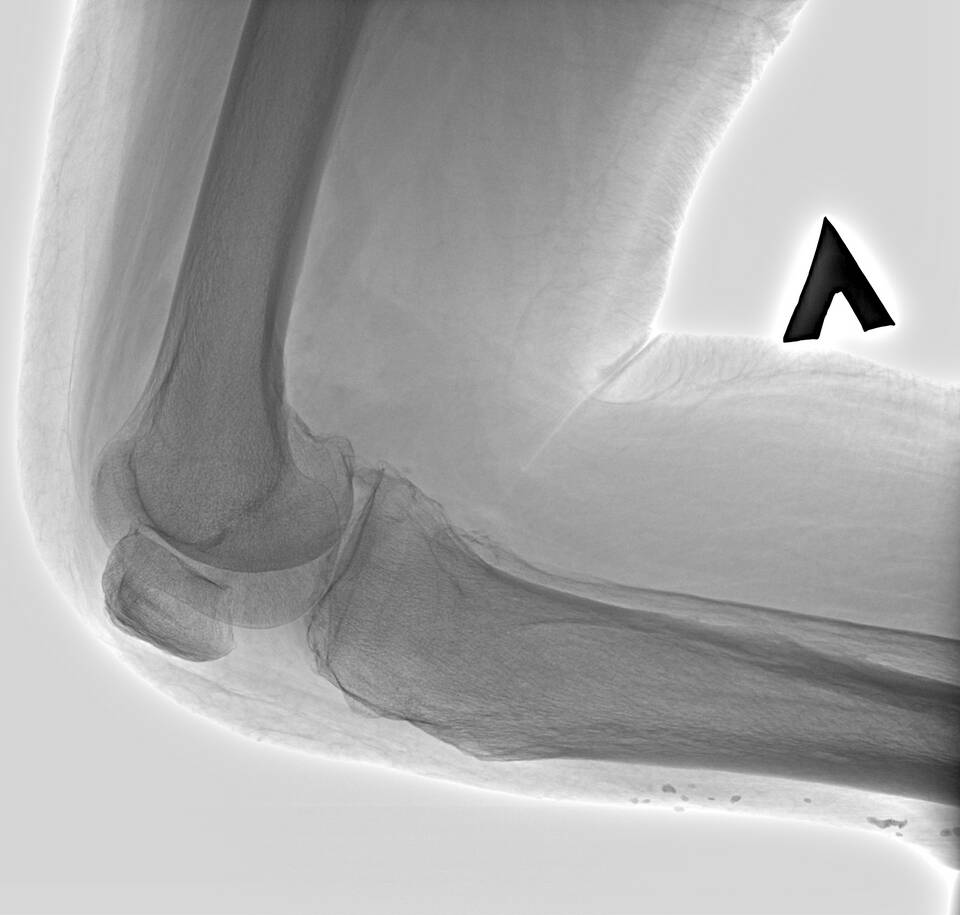

РентгенографияСужение суставной щели, остеофиты